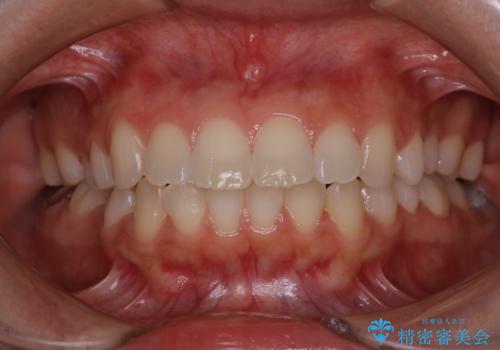

電子タバコによる着色をPMTCできれいに落とす